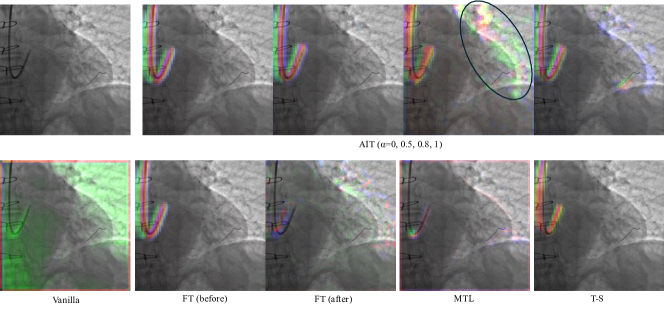

The performance of all the methods on the CPM task, along with AIT performance at different ablation strengths, is shown in Table 1. We trained CNN-C and CNN-T models using AIT and other methods for 300 and 800 epochs, respectively. It was observed that both networks failed to converge under the vanilla, FT, and MTL strategies, as evidenced by a distance metric around 25%, indicating that the networks were essentially making random guesses. The T-S method produced predictions above random chance, yet its performance was significantly inferior to that of AIT (paired t-test, p<0.05𝑝0.05p<0.05) and did not meet clinical standards. To better understand the underlying causes, we visualized the features after the second ConvLSTM block in the CNN-C backbone (Fig. 2), which was done by concatenating the magnitude of the first three principal components as RGB channels. It can be observed that AIT(α=1𝛼1\alpha=1) was able to learn strong features related to cardiac phase, located at catheter, wire, heart contour (circled in Fig. 2), whereas other methods learned much weaker features. These observations indicate that AIT is able to facilitate model convergence by incorporating catheter features.

Refer to caption

Figure 2: Visualization of Features Learned by Different Methods in the CPM task. First row (left to right): original image and AIT (α𝛼\alpha=0, 0.5, 0.8, 1). Second row (left to right): vanilla supervised learning, FT (before and after fine-tuning), MTL, and T-S.

Additionally, it is observed that AIT’s performance dip initially with the start of auxiliary input ablation but improved near the end of the ablation schedule. Together with the feature maps in Fig. 2, it suggests that the model initially relied on catheter features, which became weaker due to mask ablation. Subsequently, the model adapted by leveraging alternative features to offset the weakened catheter features, resulting in more robust predictions than those based solely on catheter information.